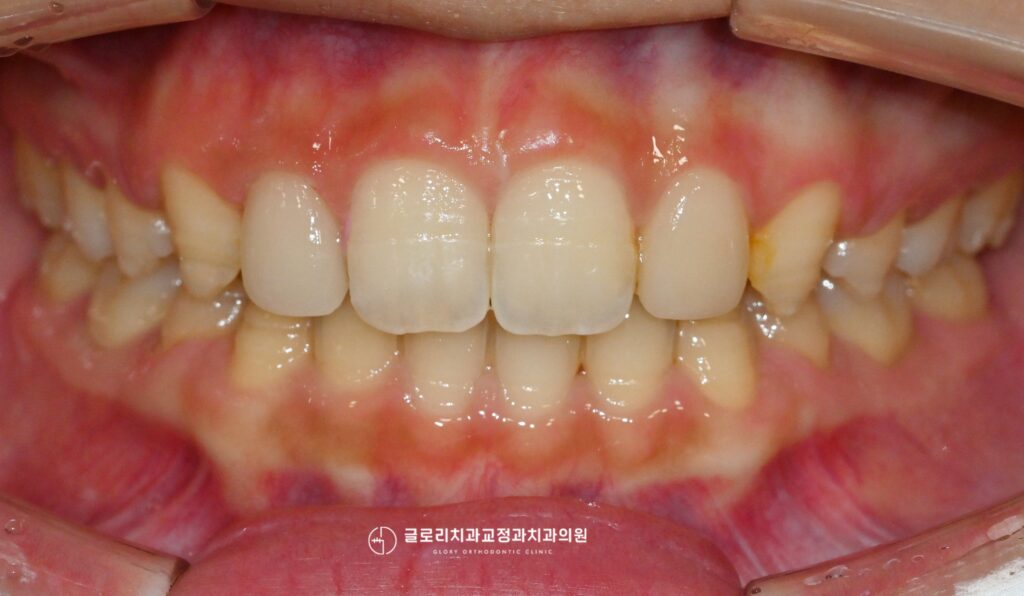

준비된 사진을 보면 현재 상악 전치부 사이가 벌어져있으며, 전반적으로 전방으로 뻗어 있는 양상을 보이고 있습니다.

또한 우측 측절치는 인접치에 비해 크기가 작은 왜소치 형태를 띠고 있어 자연치 비율의 불균형이 더욱 두드러져 보이죠.